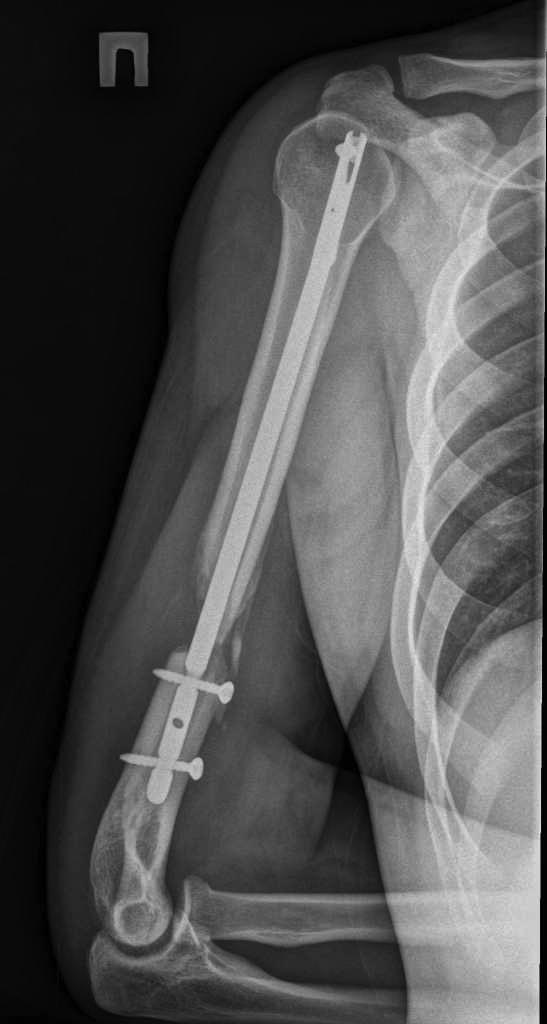

> Здравствуйте уважаемые форумчане. Представляю Вашему вниманию очередной

> сломанный

> штифт. Пациент 25 лет, в сентябре 2012 г ДТП. Кроме всего прочего,

> открытый перелом правого

> плеча с дефектом костной ткани. При поступлении выполнено ПХО и ЧКО из 2

> колец. После

> заживления раны выполнен БИОС плеча. Штифт сОлидный, Остеомед. Пару дней

> назад во время

> попытки открытия крышки банки (нагрузка по ротации) почувствовал боль в

> плече. Результат на

> снимке. Планируем удалить оба отломка (дистальный открыто) и

> перештифтовать более

> массивным штифтом. Вопрос 1: есть ли вариант в данном случае закрыто

> удалить дистальный

> франгмент НЕканюлированного штифта. Особых инструментов для удаления

> сломаных штифтов не

> имеем. Вопрос 2: как вариант рассматриваем выполнить ЧКО удалив

> предварительно только

> проксимальный фрагмент штифта. СтОит ли? Вариант накостного остеосинтеза с

> пластикой и без

> не рассматриваем. Спасибо за внимание.